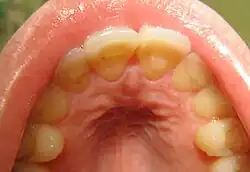

| Loss of enamel (acid erosion) from the inside of the upper front teeth as a result of bulimia | |

People with bulimia are at a higher risk to have an affective disorder, such as depression or general anxiety disorder. One study found 70% had depression at some time in their lives (as opposed to 26% for adult females in the general population), rising to 88% for all affective disorders combined.[24] Another study in the Journal of Affective Disorders found that of the population of patients that were diagnosed with an eating disorder according to the DSM-V guidelines about 27% also suffered from bipolar disorder. Within this article, the majority of the patients were diagnosed with bulimia nervosa, the second most common condition reported was binge-eating disorder.[25] Some individuals with anorexia nervosa exhibit episodes of bulimic tendencies through purging (either through self-induced vomiting or laxatives) as a way to quickly remove food in their system.[26] There may be an increased risk for diabetes mellitus type 2.[27] Bulimia also has negative effects on a person's teeth due to the acid passed through the mouth from frequent vomiting causing acid erosion, mainly on the posterior dental surface.